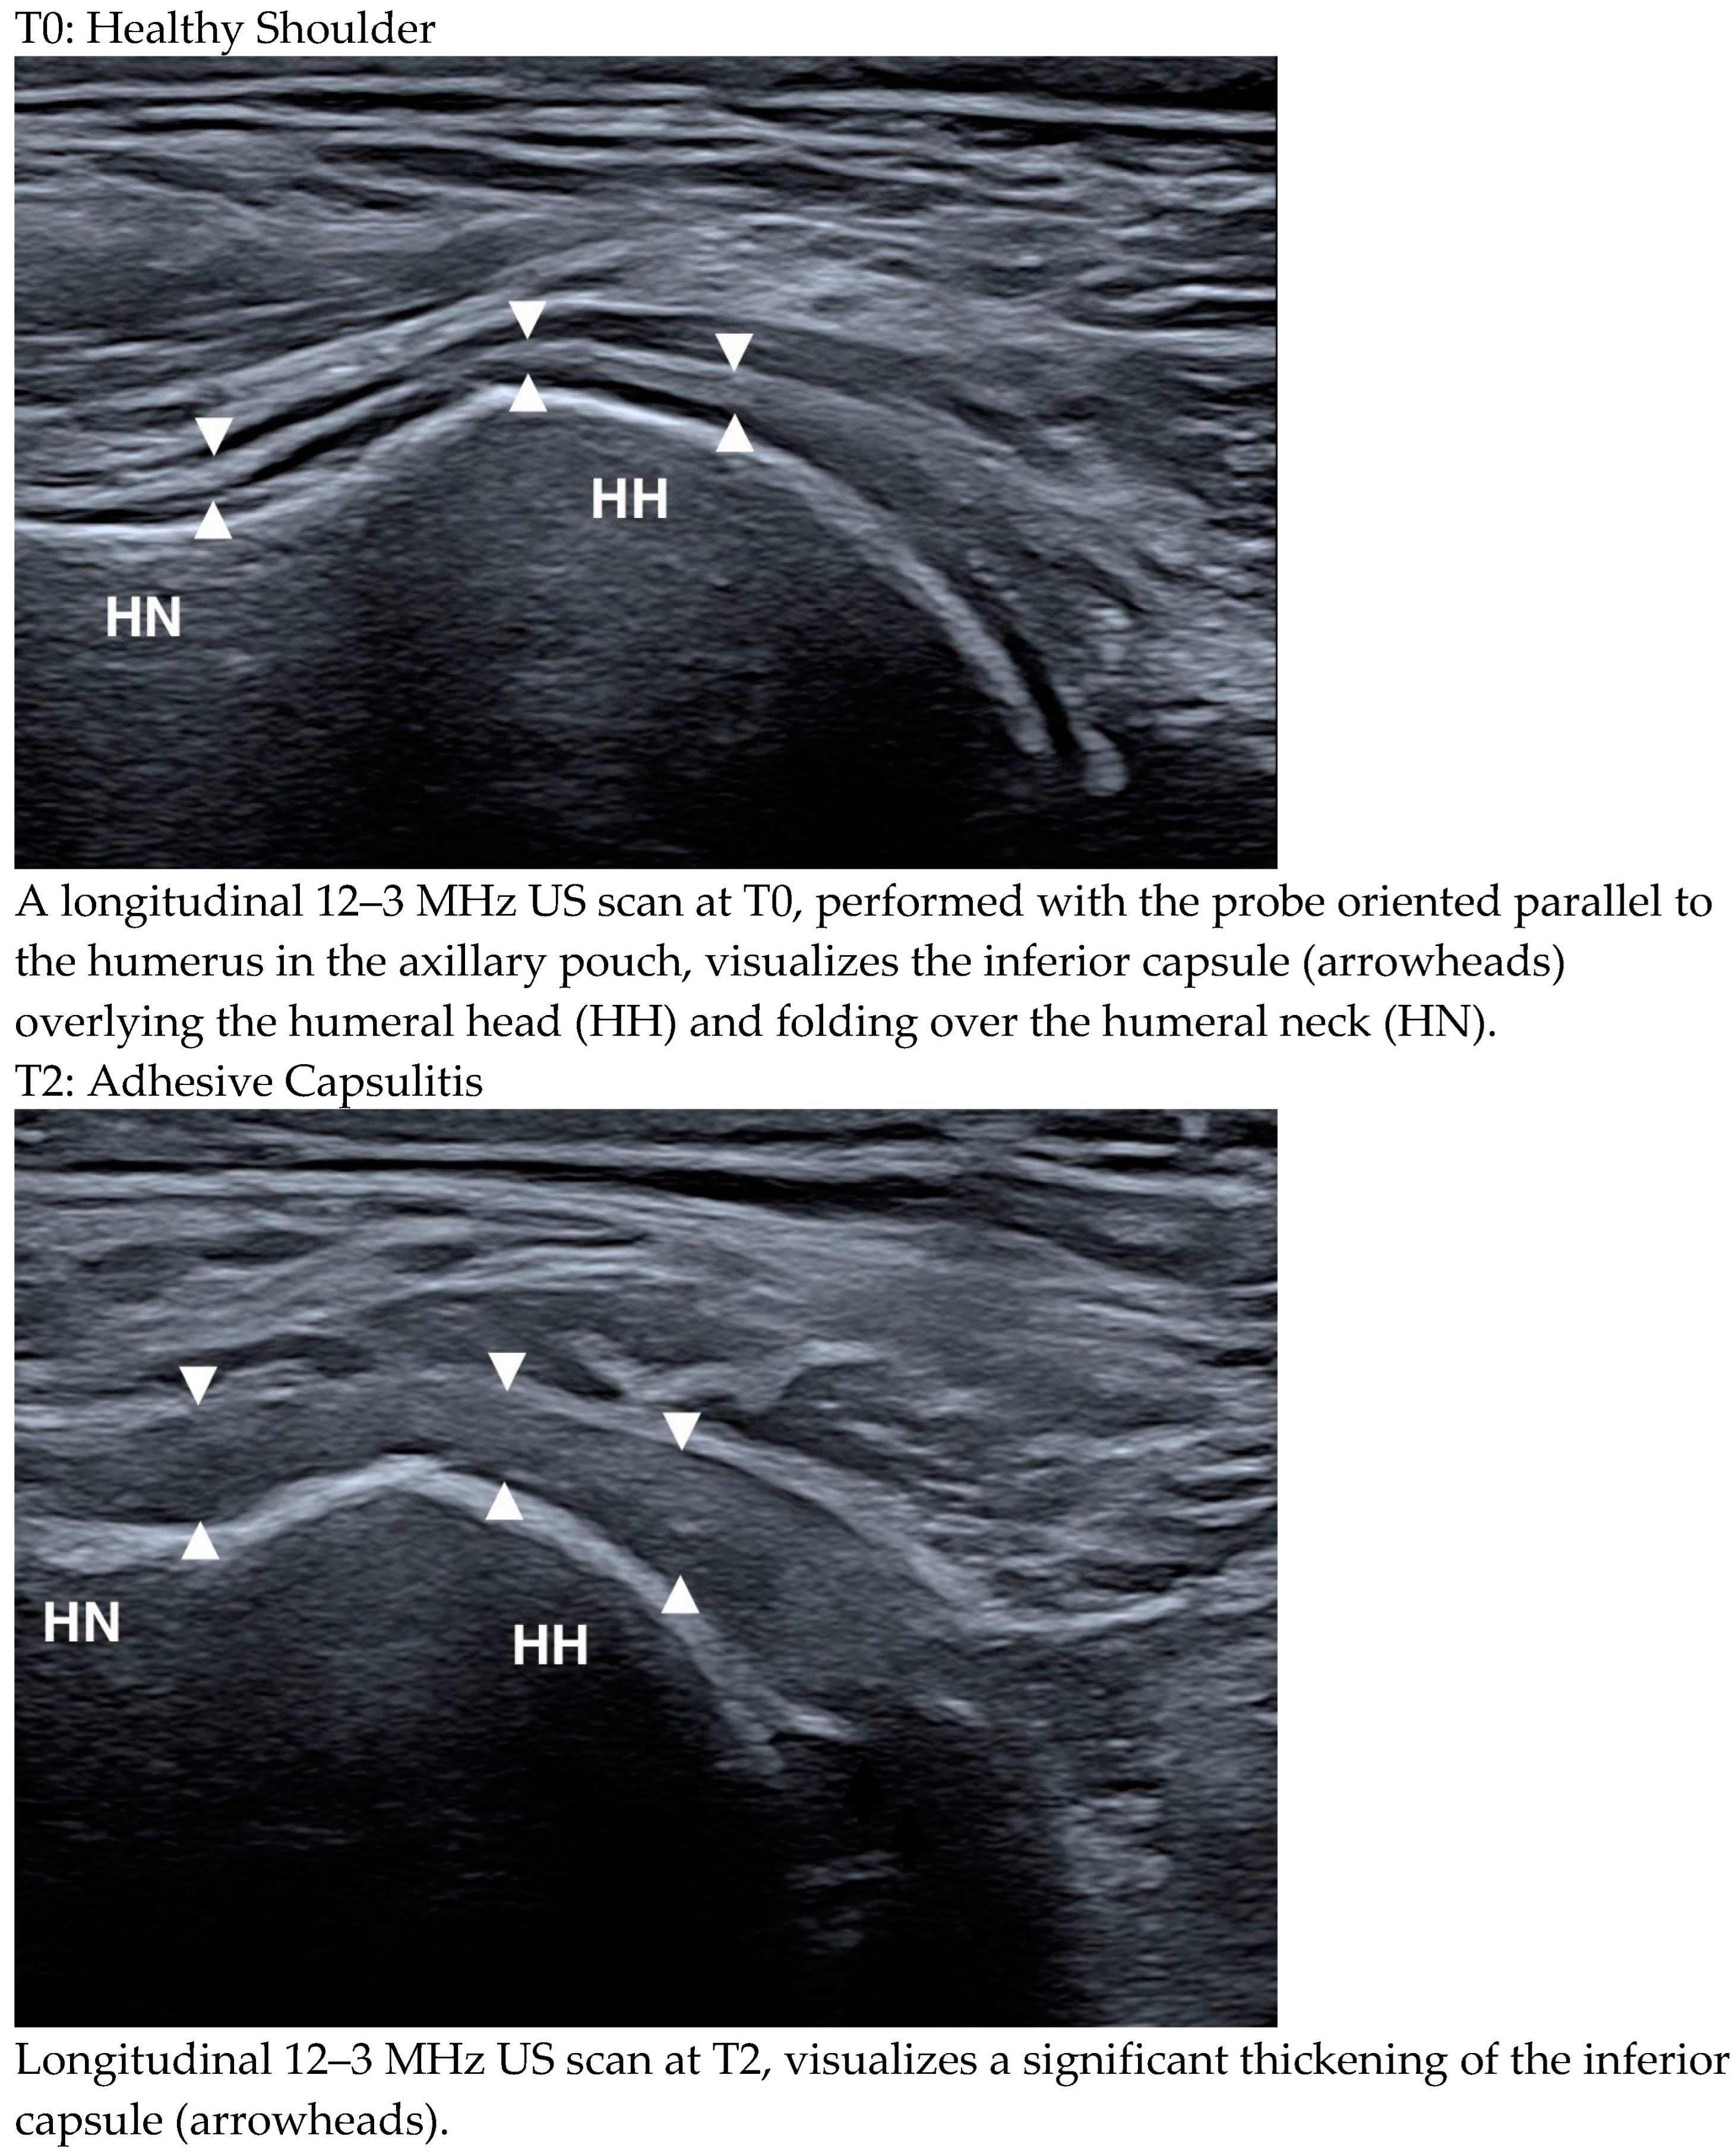

- Picasso, R.; Pistoia, F.; Zaottini, F.; Marcenaro, G.; Miguel-Pérez, M.; Tagliafico, A.S.; Martinoli, C. Adhesive Capsulitis of the Shoulder: Current Concepts on the Diagnostic Work-Up and Evidence-Based Protocol for Radiological Evaluation. Diagnostics 2023, 13, 3410. [Google Scholar] [CrossRef] [PubMed]

- Stella, S.M.; Gualtierotti, R.; Ciampi, B.; Trentanni, C.; Sconfienza, L.M.; Del Chiaro, A.; Pacini, P.; Miccoli, M.; Galletti, S. Ultrasound Features of Adhesive Capsulitis. Rheumatol. Ther. 2022, 9, 481–495. [Google Scholar] [CrossRef] [PubMed]